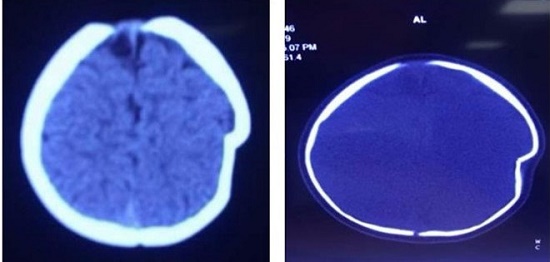

Hình ảnh lún sọ não trước mổ - Ảnh: Zing.vn |

Thông tin từ khoa Ngoại Thần kinh - Bệnh viện đa khoa tỉnh Phú Thọ cho biết, ngày 18/9 các bác sĩ của khoa đã phẫu thuật để nâng xương lún cho bệnh nhi 8 tháng tuổi bị ngã lún sọ thái dương đỉnh trái.

Mẹ của bé (ở Thanh Thủy, Phú Thọ) cho biết tai nạn xảy ra khi chị để con ngồi trên xe tập đi một mình và không kiểm tra mối dây buộc khiến chiếc xe lao xuống sân với ở độ cao khoảng 1 m. Cú va chạm mạnh với mặt đất đã khiến chóp đầu trái của bé bị lún sâu 1 cm.

Bác sĩ Hà Xuân Tài, Phó khoa Ngoại Thần kinh, bác sĩ trực tiếp phẫu thuật cho bệnh nhi này, cho biết lún sọ thường gặp ở trẻ nhũ nhi dưới một tuổi. Nguyên nhân thường là tai biến sinh có thủ thuật, trẻ bị ngã khi tập đứng, tập đi và ngã ở độ cao thấp. Vị trí thường bị lún ở hộp sọ là vùng đỉnh.

Do ở trẻ nhũ nhi, hộp sọ có khả năng tự điều chỉnh tốt nên hiếm khi phải mổ cấp cứu ngay, trừ những trường hợp lún sọ mức độ nhiều, tổn thương rách màng cứng và tổn thương não. Tuy nhiên, cha mẹ thường rất lo lắng và yêu cầu được mổ ngay vì liên quan đến thẩm mỹ hộp sọ và sợ ảnh hưởng đến thần kinh của trẻ về sau.

Với trường hợp bé 8 tháng này, các bác sĩ đã tiến hành phẫu thuật để nâng xương lún vào ngày 4/9. Đến chiều 12/9, khi sức khỏe ổn định trở lại, bé được xuất viện.